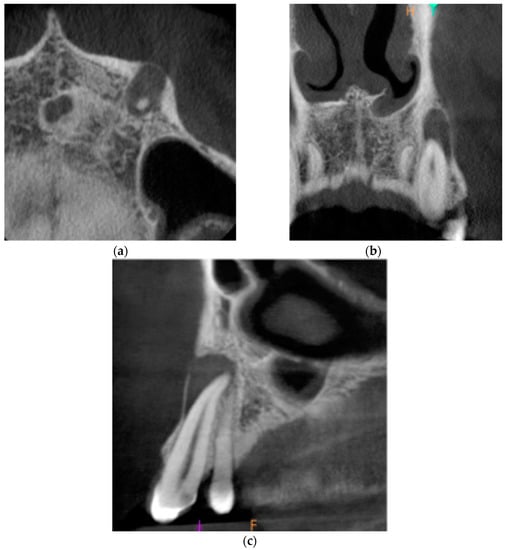

The third and final appointment was scheduled 6 months after the end of root canal treatment. Intraoral examination revealed healing progression. The gingiva was smooth, pink, and humid, with no pain on palpation. The mobility of the tooth was within the physiological limits (Grade 1 Miller mobility index). The reaction of tooth 23 to vertical and horizontal percussion was negative. PD max = 4 mm. The CBCT images presented healing of the periapical lesion. There was a small area of radiolucency around tooth no. 23 with the dimensions of 2.6 × 1.0 × 0.6 mm. Figure 4 presents the CBCT images of the periapical lesion healing process 6 months after the end of endodontic treatment.

Figure 4. CBCT images presenting the healing process of the periapical lesion around the root of tooth no. 23 (date of CBCT examination: 8 December 2020): (a) axial view; (b) coronal view; and (c) sagittal view.